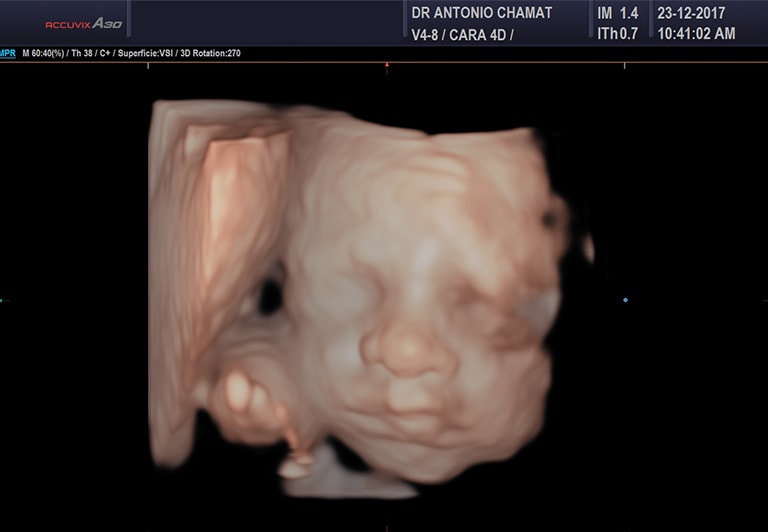

Ecografía 4D

Es una ecografía 3D en movimiento, o sea, en tiempo real, que posibilita observar al bebé mientras abre la boca o los ojos y realiza diferentes acciones, mostrando a los padres una imagen más clara y comprensible de la vida del bebé en el útero.

Ecografía 5D

Es una ecografía en tiempo real y High Definition (conocida como FRV o Fetal Realistic View) que muestra al bebé en movimiento. Se logran imágenes casi como si estuviera ya nacido.

El estudio ecográfico 5D permite una mayor compenetración de la familia con el bebé, dejando un maravilloso recuerdo en video y fotografías a color, al mismo tiempo que brinda seguridad y tranquilidad a los padres sobre el bienestar del nuevo miembro de la familia. A esta cita generalmente van acompañados de los demás hijos de la pareja, abuelos y otros familiares, porque es una excelente oportunidad para apreciar la imagen más real del bebé.

Esta ecografía siempre se acompaña de una de Detalle anatómico – Nivel 3, en la cual se descartan malformaciones.